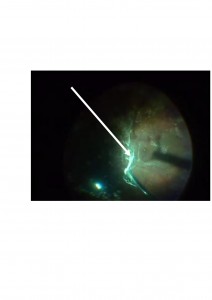

Os mostramos unas imágenes de un paciente atendido en nuestro Hospital.

La segunda se corresponde con la cirugía de dicho paciente. Podéis observar cómo despegamos el vítreo, que lo visualizamos con la ayuda de acetónido de triamcinolona (cristales blanquecinos), de la retina.